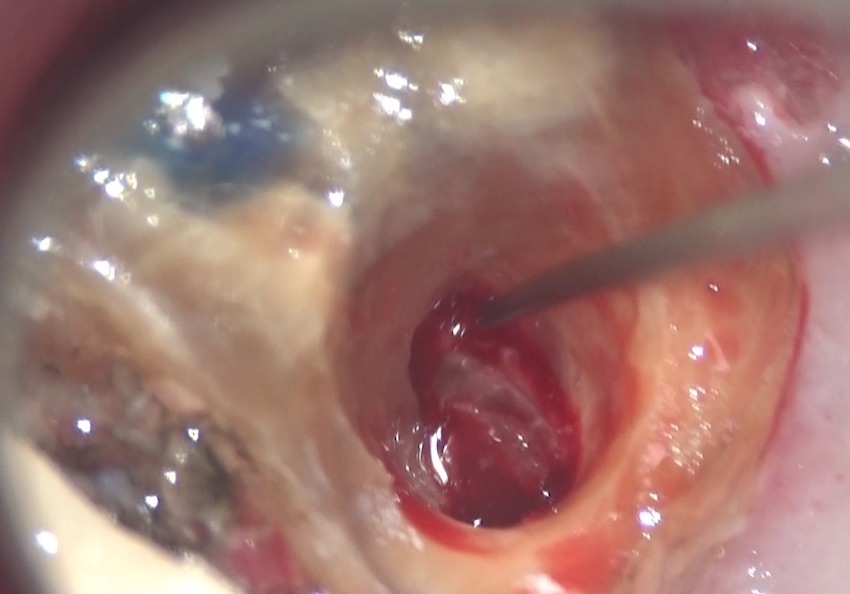

3〜4ヶ月、矯正的に引っ張り上げ、歯茎から、歯を出して、治療しました。

この後、通常の根管治療を行いました。この治療については、後日お話致します。